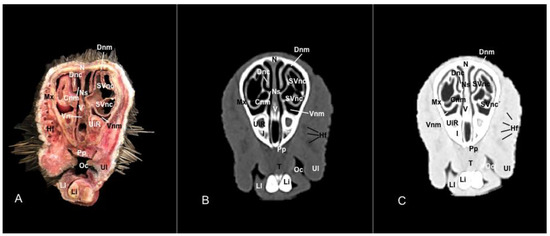

3.1. Anatomical Sections

3.2. Computed Tomography (CT)